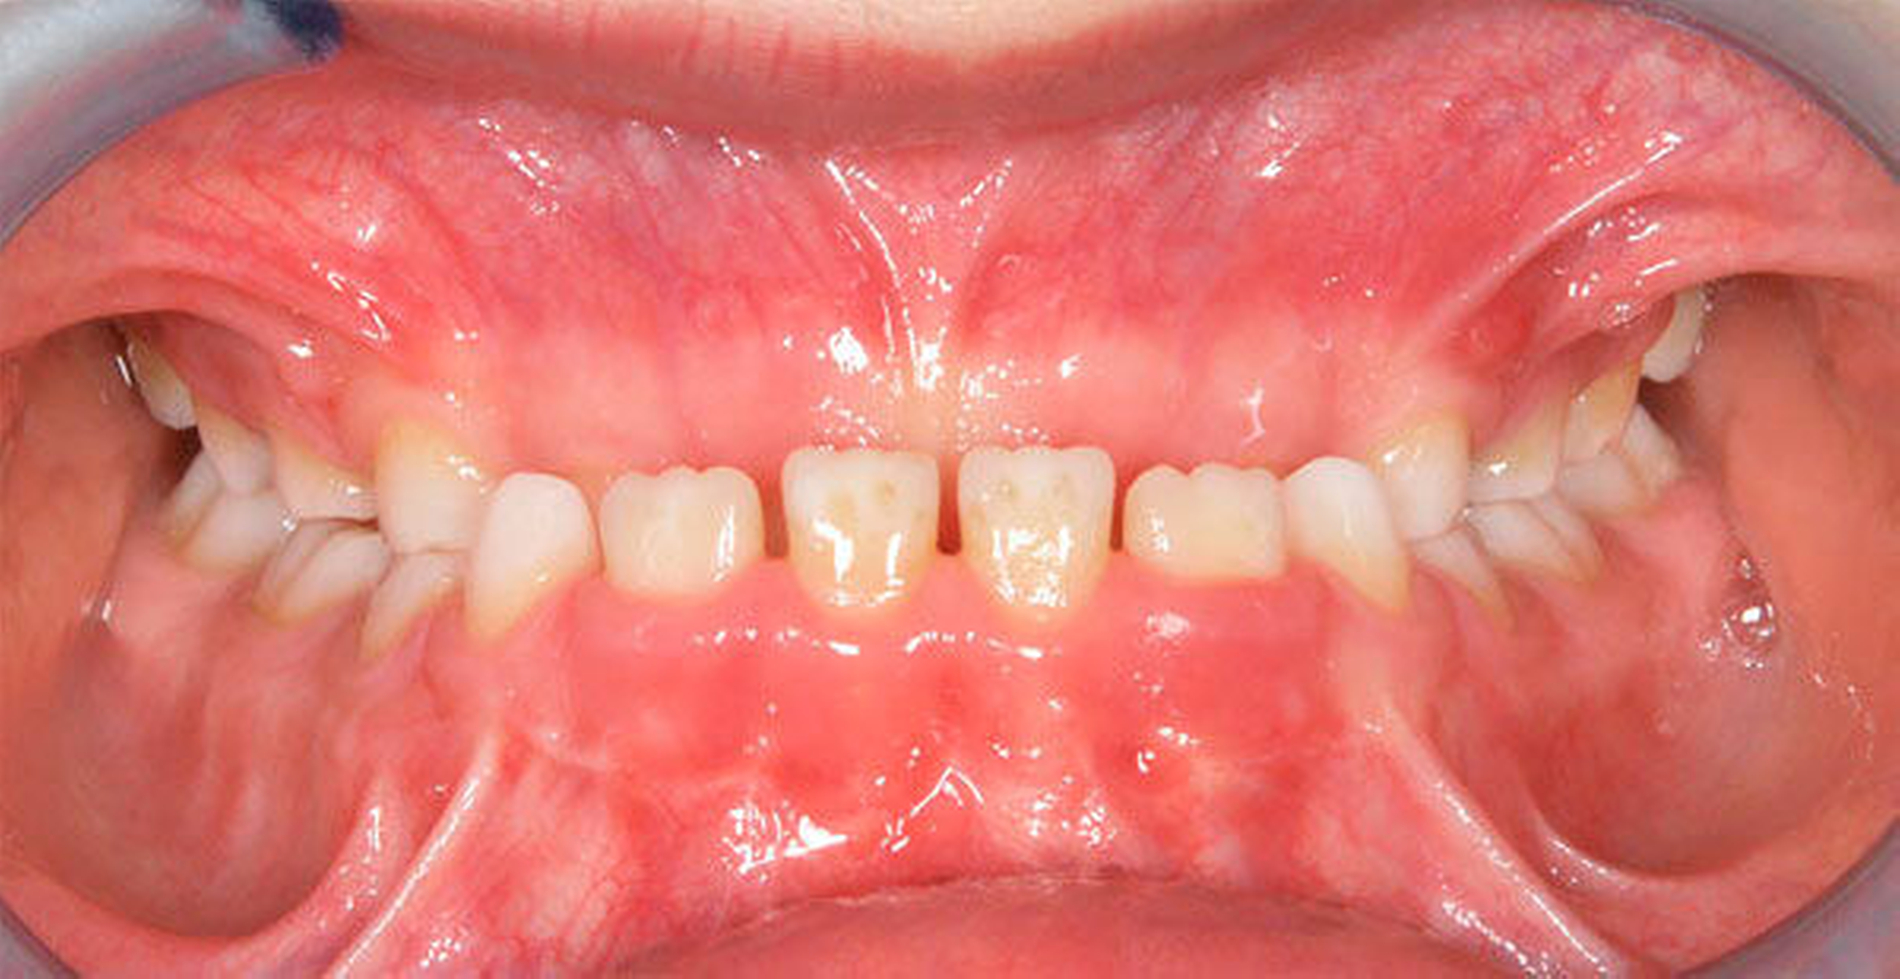

Neben der Beurteilung der Platzverhältnisse sollte auch die Okklusion in allen drei Dimensionen (vertikal, transversal und sagittal) überprüft werden, denn bereits in dieser frühen Phase können Dyskinesien und statische Funktionsstörungen die Entwicklung nachhaltig stören [Grabowski, 2007]. Ungünstige Umwelteinflüsse und Milieufaktoren spielen bei vielen kieferorthopädischen Anomalien eine wichtige Rolle, wobei es oft schwierig ist, den Anteil von umweltbedingten Faktoren/Milieufaktoren und genetischer Disposition exakt zu bestimmen. Allerdings wird der offenen Mundhaltung, die mit einem inkompetenten Lippenschluss und kaudaler Zungenruhelage vergesellschaftet ist, ein besonders nachteiliger Einfluss auf die physiologische Entwicklung zugeschrieben. Besonders häufig werden bei diesen statischen Haltungsschwächen das Auftreten eines transversal unterentwickelten Oberkiefers, ein vergrößerter oder reduzierter Overjet sowie ein offener Biss beobachtet [Grabowski, 2008]. Insbesondere beim offenen Biss wirkt sich zudem eine gewohnheitsmäßige oder anatomisch bedingte Mundatmung nachteilig auf die vertikale Entwicklung des Gesichts aus [Linder-Aronson, 1983]. Bei Verdacht auf eine anatomisch bedingte Mundatmung sollte zusätzlich HNO-ärztlich überprüft werden, ob organische Blockaden beseitigt werden können. Persistierende Lutschgewohnheiten können ebenfalls einen ungünstigen Einfluss auf den orofazialen Reifungsprozess nehmen [Dausch-Neumann, 1983]. Neben einer vergrößerten Frontzahnstufe (Abbildung 2) oder einem anterior offenen Biss als direkte Lutschfolgen erfolgt zudem meist keine Umstellung auf ein somatisches Schluckmuster, wobei diese sekundären Lutschfolgen später nur schwer und nur mit hohem Aufwand therapiert werden können [Cozza, 2005]. Auch hierbei kann zum Beispiel das Eingliedern einer Mundvorhofplatte (MVP) als interzeptive Maßnahme das Abgewöhnen von Gebiss schädigenden Gewohnheiten unterstützen [Dausch-Neumann, 1983].